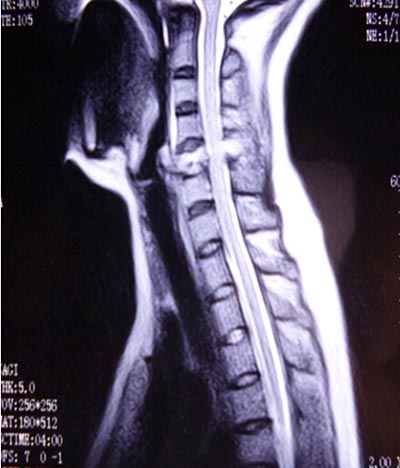

近日,我院骨二科成功完成一例前后联合入路颈椎肿瘤切除重建术。该患者来自陕西汉阴,女,45岁,1月前无明显诱因感颈肩部疼痛不适,在当地医院就诊行相关检查诊断:“颈5椎体病理性骨折”,考虑手术的风险及难度极高,建议转至我院。磁共振检查示“颈5椎体及附件破坏并塌陷”,椎动脉血管造影示“右侧椎动脉发育不良,颈5椎体及附加破坏并包绕椎动脉”。积极术前准备工作,全科讨论后制定前后联合入路肿瘤切除重建手术方案。手术于2014.10.20日如期进行,张晓琴教授负责麻醉,术中进行动脉血压监测、中心静脉压监测、动态血气分析、全面的的生命体征监测,确保了手术安全和平稳。手术由李浩鹏教授指导,王栋副教授主刀,赵波主治医师协助。先取颈部前侧入路,于气管鞘及食管鞘间隙进入,切除颈5椎体,术中可见颈5椎体破坏,彻底切除病变组织至双侧横突,显露椎动脉及神经根,小心完整切除右侧椎动脉包绕的鱼肉样病变组织,更换手套,取左侧髂骨修剪为颗粒状及短棒状置入钛网放置于颈5椎体缺损部,前方钛板固定进行重建。再取俯卧位,颈部后正中切口,彻底切除颈5棘突及双侧椎板至双侧横突,双侧侧块钢板固定。手术顺利,术前症状显著改善,术后第二天即可在颈托保护下下地活动。该部位解剖复杂,血管、神经多,不易分离,有可能损伤椎动脉,脊髓及神经根,引起截瘫、大出血,脑坏死等,风险很大。术中以最精准的操作,解剖性、根治性切除病灶,同时进行了骨性重建,保证了颈椎的稳定性。该肿瘤的成功切除及重建,显现了我院骨二科的综合技术实力,以及团结协作、严谨求实、不断进取的专业精神,也标志着我院的脊柱外科达到国内先进水平。